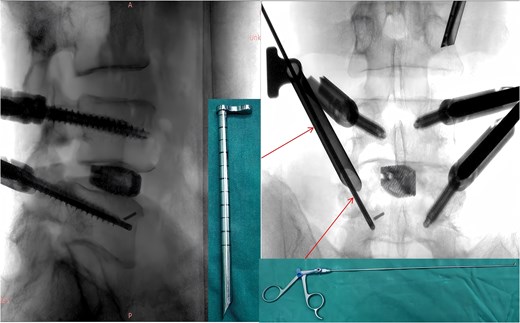

A 49-year-old male presented with a 10-month history of low back pain accompanied by numbness in the left lower limb. Over the past 2 weeks, his symptoms had progressively worsened without any identifiable precipitating factor, with increasing pain and numbness radiating down the left lower extremity. The patient reported that walking about 20 meters aggravated his symptoms, which were relieved after rest, allowing him to walk another short distance before the pain recurred. Due to the lack of significant relief from over-the-counter analgesics and topical medications, he presented to our outpatient clinic for further evaluation. Clinical examination and preoperative imaging demonstrated lumbar spinal stenosis at the L4/L5 level, lumbar instability, and grade I spondylolisthesis at L4 (Fig. 1). Following a comprehensive preoperative assessment, the patient was scheduled for PE-PLIF.

Preoperative anteroposterior and lateral radiographs of the lumbar spine.